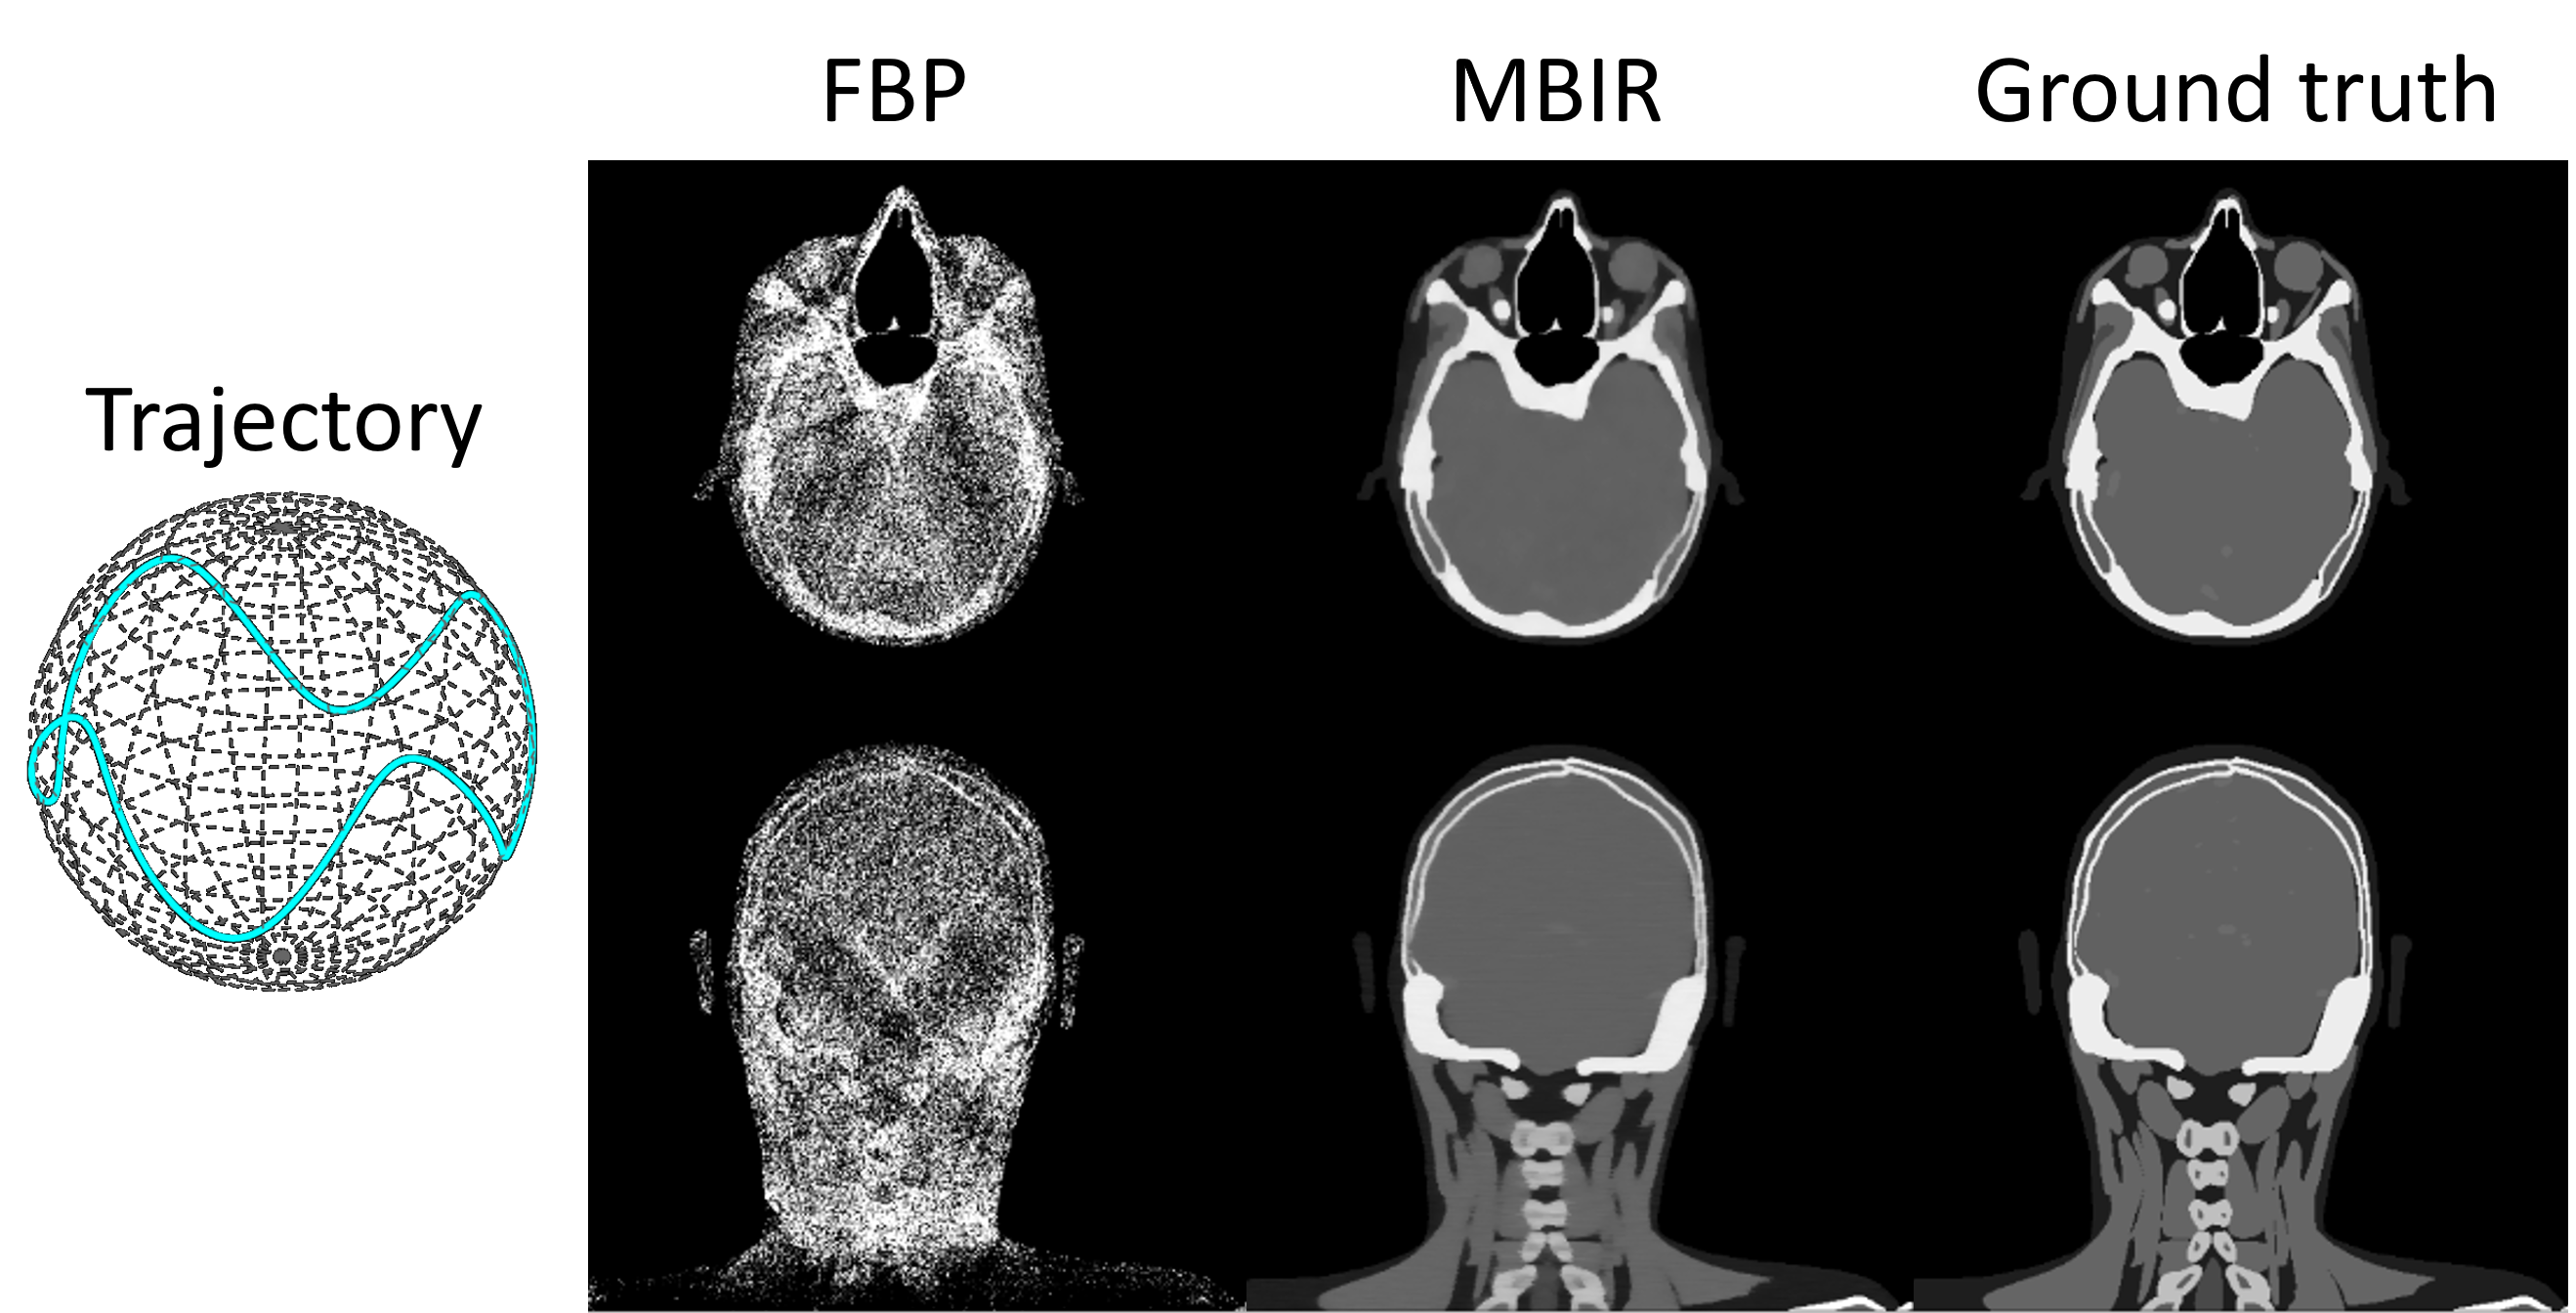

Finally, we validate the effectiveness of auto-differentiation through MBIR. As illustrated in Fig. 7, 200 head[24] cone-beam projections are simulated with a sinusoidal scan trajectory. The objective function of MBIR is formulated as:

x=argminxAxy22+λxTVsuperscriptxsubscriptargminxsuperscriptsubscriptnormAxy22𝜆subscriptnormx𝑇𝑉\textbf{x}^{*}=\text{argmin}_{\textbf{x}}\|\textbf{Ax}-\textbf{y}\|_{2}^{2}+% \lambda\|\textbf{x}\|_{TV}x start_POSTSUPERSCRIPT ∗ end_POSTSUPERSCRIPT = argmin start_POSTSUBSCRIPT x end_POSTSUBSCRIPT ∥ Ax - y ∥ start_POSTSUBSCRIPT 2 end_POSTSUBSCRIPT start_POSTSUPERSCRIPT 2 end_POSTSUPERSCRIPT + italic_λ ∥ x ∥ start_POSTSUBSCRIPT italic_T italic_V end_POSTSUBSCRIPT (3)

The objective function is minimized with 200 iterations of the Adam optimizer where the gradient is computed via auto-differentiation (as shown in the Sec.2.4). Due to the irregular projection sampling pattern, FBP reconstruction exhibits substantial non-uniformity. In contrast, MBIR effectively improves the reconstruction accuracy, as evidenced by a clear depiction of bone and soft tissue boundaries. These results validate the effectiveness of auto-differentiation in conjunction with the CTorch projector.

Figure 7: FBP and MBIR reconstruction of projections simulated with a non-circular scan trajectory.